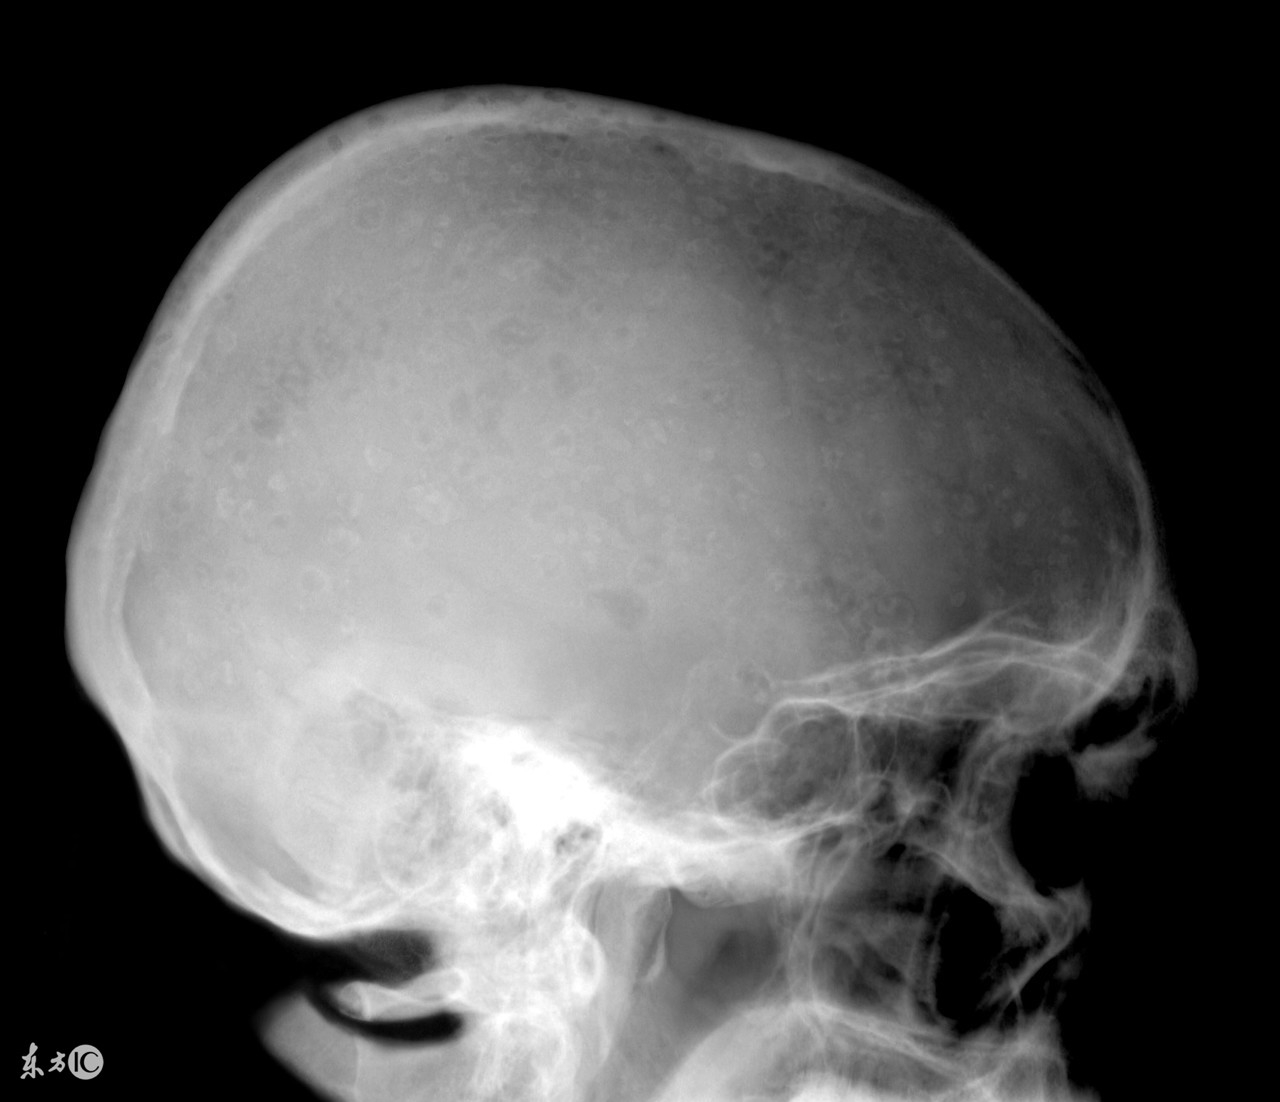

越来越多的人受到了多发性骨髓瘤的困扰,我们大家都知道,患了多发性骨髓瘤会对我们的身体和心理健康造成很大的危害,因此发现患病之后一定要积极的进行治疗,而且多发性骨髓瘤的治疗也是有一定难度的,那么,多发性骨髓瘤大概需要花费多少钱?

治疗多发性骨髓瘤费用其实和患者的病情严重程度有着密切的关联,而且较为严重的时候还会引起消化系统、心血管系统、运动系统等多器官病变,严重可导致死亡。所以想要了解治疗多发性骨髓瘤疾病究竟需要多少钱是需要根据患者病情的严重程度才能确定,因为针对不同程度的治疗多发性骨髓瘤的方法不同,相对应的费用也是不一样的,所以当患上这种疾病之后,一定要第一时间到医院接受治疗,避免病情恶化而导致治疗难度增大,费用增多。